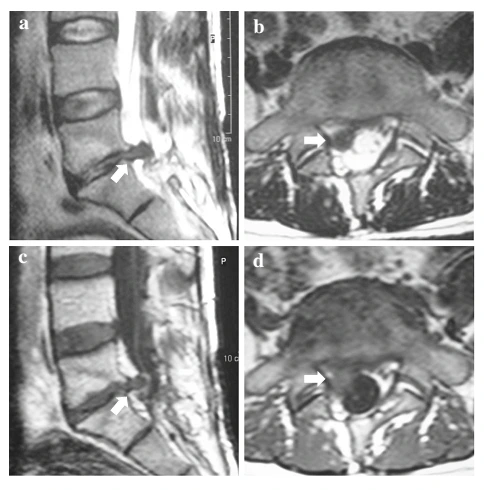

이 사진은 45세 환자의 사진입니다.

요추 5번하고 천추 1번 사이에 튀어나온 디스크가 있어서

수술을 받았는데요.

윗 사진은 수술을 받기 전 사진이고,

아래 사진은 수술을 받고 난 뒤 2년 뒤 사진입니다.

같은 부위에 같은 방향으로 디스크 탈출증이 나와있지요?

이런 것을 RLDH라고 합니다.